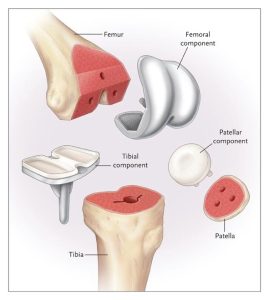

پروتزهای مفصل زانو :

علم طراحی و کارگذاری مفصل زانو علمی بسیار پیشرفته است که بر مبنای دو پیشرفت اساسی حاصل شده است.

یکی پیدا کردن موادی با حداقل اصطکاک سطحی. این مواد برای تمامی موارد تعویض مفصل عبارتند از پلیاتلین و فلز. پلیمر پلیاتلین هرچه دارای وزن مولکولی بیشتری باشد پایدار تر و در مقابل سائیدگی مقاوم تر است. فلز در مفاصل مختلف از فولاد ضد زنگ یا کروم کبالت و یا تیتانیوم استفاده میشود. در مفصل زانو از ترکیب پلیاتلین ultra-high density و کروم کبالت استفاده میشود. به این ترتیب که برای سطح مفصلی استخوان فمور(ران) از کومپوننت تمام فلزی استفاده میشود و برای سطح مفصلی استخوان تیبیا (ساق) از بخش فلزی برای اتصال به استخوان استفاده میشود که بر روی آن یک لایه حداقل 10 میلیمتری پلیاتلین قرار داده میشود که با کومپوننت فلزی فمور در تماس قرار میگیرد.

در کارگذاری معمول مفصل زانو در مورد مفصل پتلا (کشکک) پروتزی استفاده نشده و با اقدامات خاصی سطح مفصلی آن صاف و بدون درد میشود اما اگر قرار به تعویض سطح مفصلی آن باشد از کومپوننت پلیاتلینی استفاده میشود که در تماس با کومپوننت فلزی فمور قرار میگیرد.